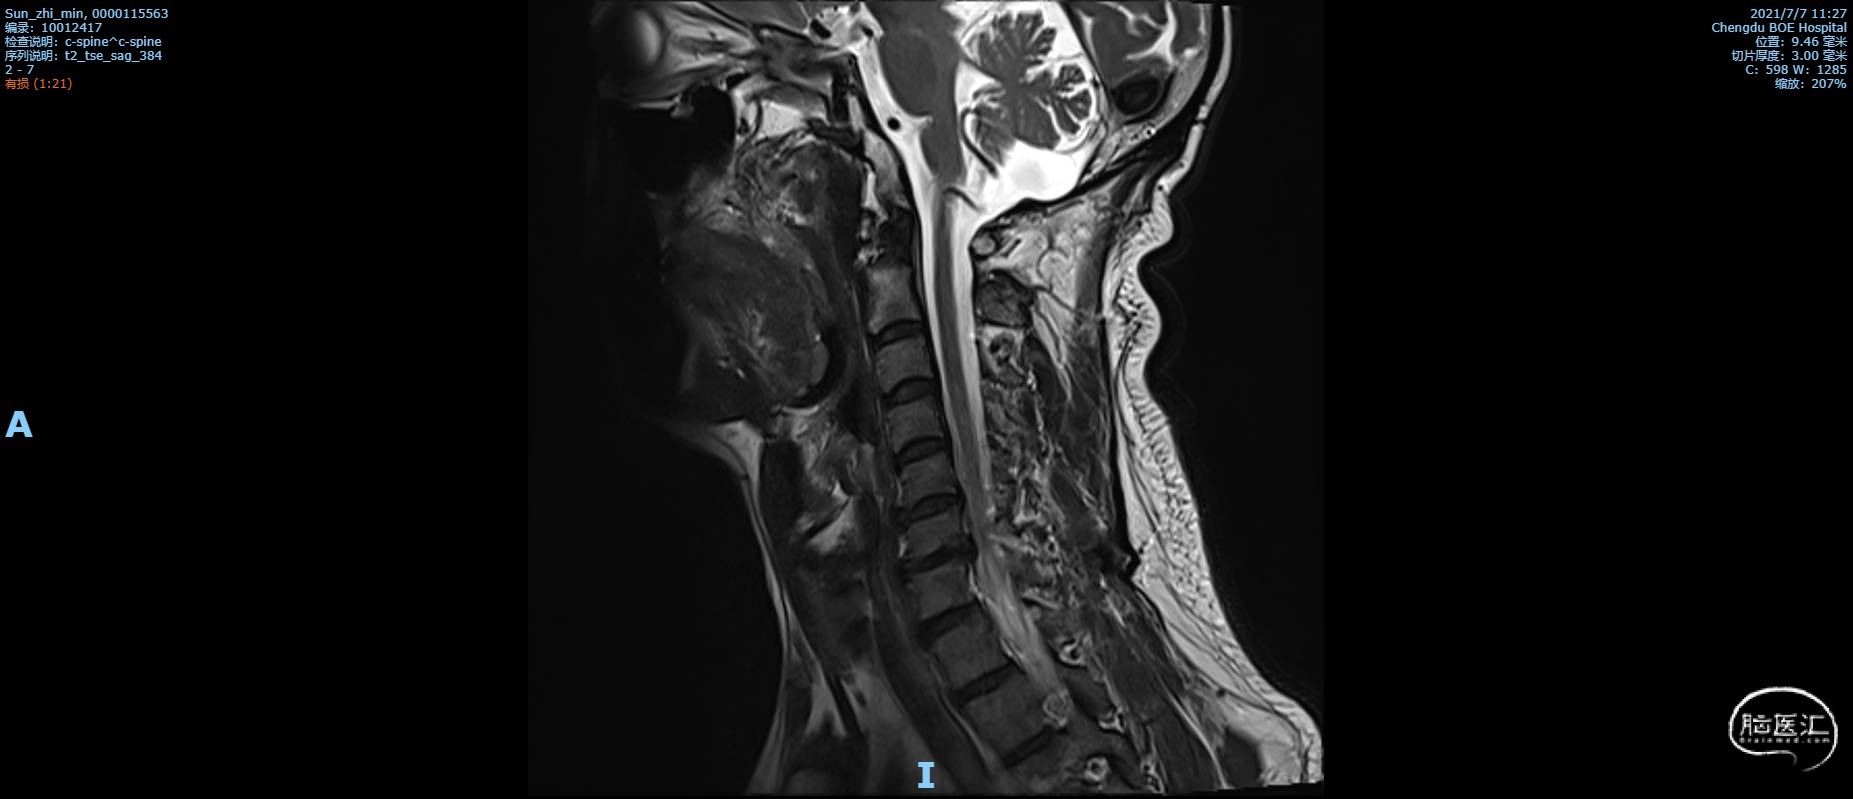

术前复查MRI矢状位颈椎MRI T2 加权像,C6椎体不稳定,C6/C7椎间盘脱出,局部脊髓受压,斑片状信号改变,颈椎管狭窄。

颈椎MRI T2 加权像1

颈椎MRI T2 加权像2

颈椎MRI T2 加权像3